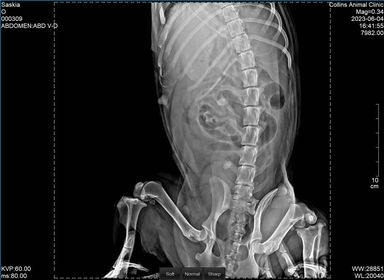

What to do if you dog or cat has a fracture in bone or joint ?

The Complete Guide about Fractures in dogs and cats

Fractures in dogs and cats